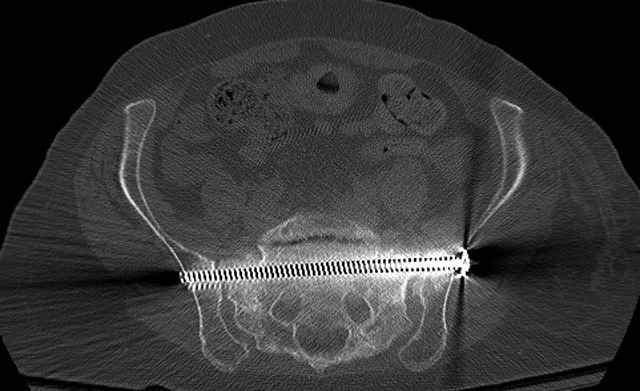

Here are a recent patient’s example slides...

3 Months After Fall

Continued Pain & Immobility

(+) Instability to Compressive Manual Exam

Pelvic CT Scan - 3 Months After Fall

Sacral Injuries

Ramus Fractures

Percutaneous Fixation

(B) Ramus-Retrograde

2 TransIliac-TransSacral

Upper Segment